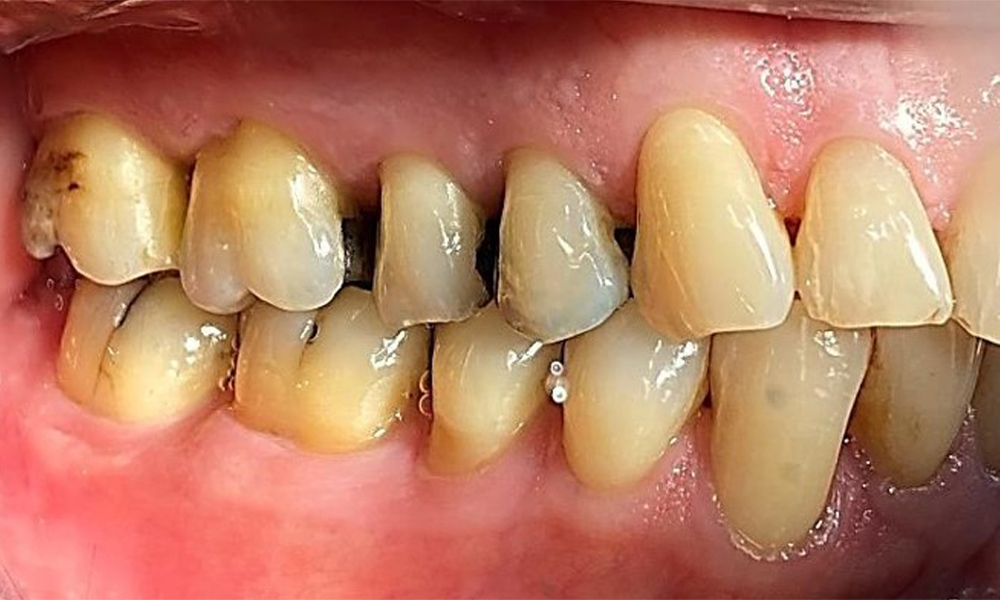

Lateralansicht rechts. Verlust der interdentalen Papillen. © Dr. R. Krapf

Abb. 3 Lateralansicht rechts. Verlust der interdentalen Papillen. © Dr. R. Krapf

Lateralansicht links mit Ansicht der Rezessionen. © Dr. R. Krapf

Abb. 4 Lateralansicht links mit Ansicht der Rezessionen. © Dr. R. Krapf

Der Patient hat ein vollbezahntes Gebiss mit 28 Zähnen, an welchen sich im Molaren- und Prämolarenbereich Amalgamfüllungen und Compositefüllungen befinden. An Zahn 14 zeigt sich ein sichtbarer klinischer Randspalt. Zahn 27 hat ein suffizientes Goldinlay. Zudem zeigen sich generalisierte Attritionen und Abrasionen. (Abb. 2, Abb. 3, Abb. 4, Abb. 5, Abb. 6)

Der Patient hat eine Parodontitis Stadium II, Grad B (5). Die klinischen Sondierungstiefen liegen mit 1-3mm im physiologischen Bereich. Lokalisierte Sondierungstiefen finden sich an 17 und 27 jeweils mesiopalatinal mit 5mm. Es liegen generalisierte Rezessionen von 1-3mm vor mit partiellem Verlust der Interdentalpapillen (Abb. 2, Abb. 3, Abb. 4)